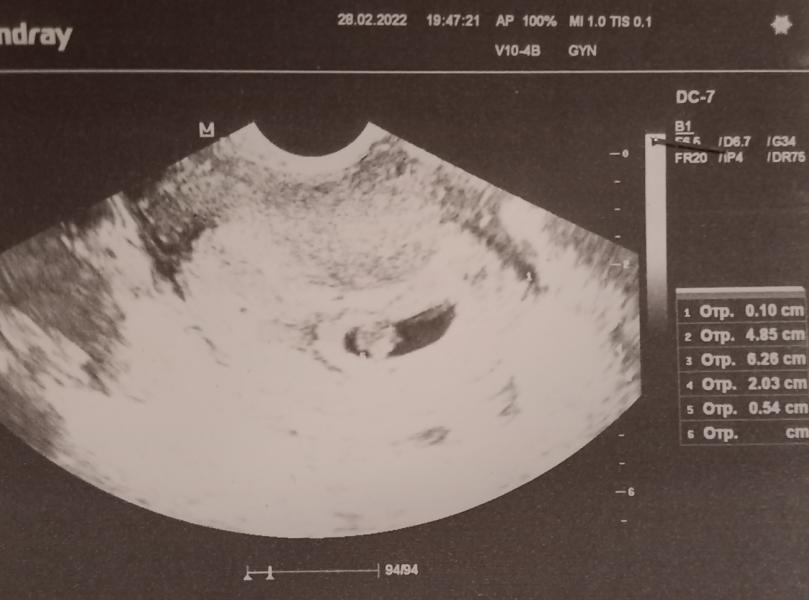

6-7 недель беременности: что происходит?

6-7 недель💣💙💖